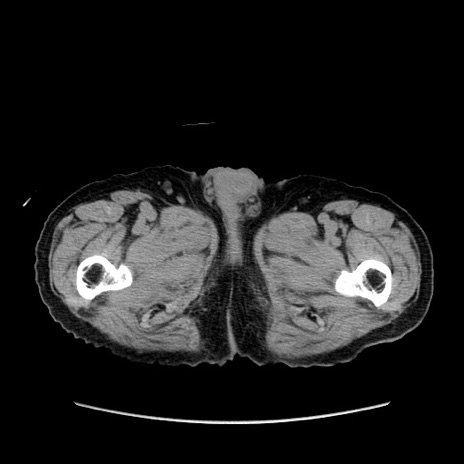

症例24(横断像)

【症例】80歳代男性

【主訴】左側腹部痛、嘔吐

【現病歴】本日早朝より左腹部に痛みあり。昼頃嘔吐認めたため、救急要請。

【既往歴】直腸癌(Mile手術)、胆摘

【身体所見】意識清明、BT 35.9℃、BP 221/93mmHg、SpO2 97%(RA) 、腹部:左ストーマ周囲に限局性の腹部膨隆あり。 膨隆部自発痛・圧痛あり・軟。

【データ】WBC 7700、CRP 0.09